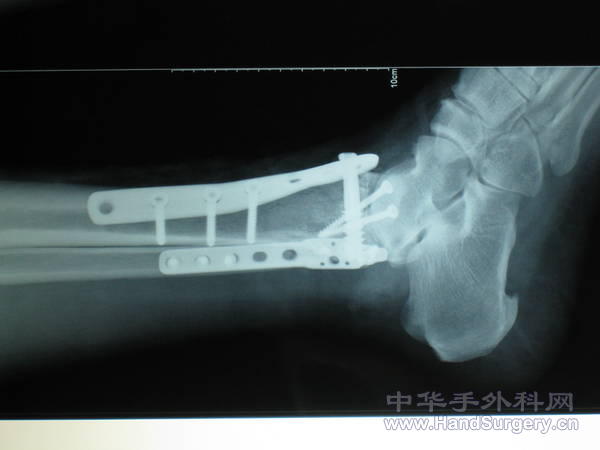

pilon骨折一例-手足外科魏宝富主任作品

楼主的手术做得很好,创伤性关节炎可能是再所难免了。

魏主任:你的手术做的很好,但是不知关节面是如何处理的,植骨了吗?是急症做的还是消肿以后做的?切口愈合如何?还有外侧的关节面好像没有处理?

胫骨远端外侧解剖钢板过前,如果锁定钢板会好很多,植骨不知道什么情况

对于此类骨折,手术最关键所在应该是先恢复腓骨解剖位置,其余骨折块做起来较容易些。另外需要注意植骨支撑,再者注意下胫腓关系一定要稳定!不要轻易去做融合!个人理解